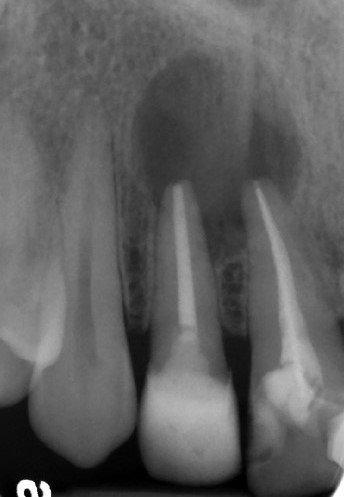

牙科放射線學(二)